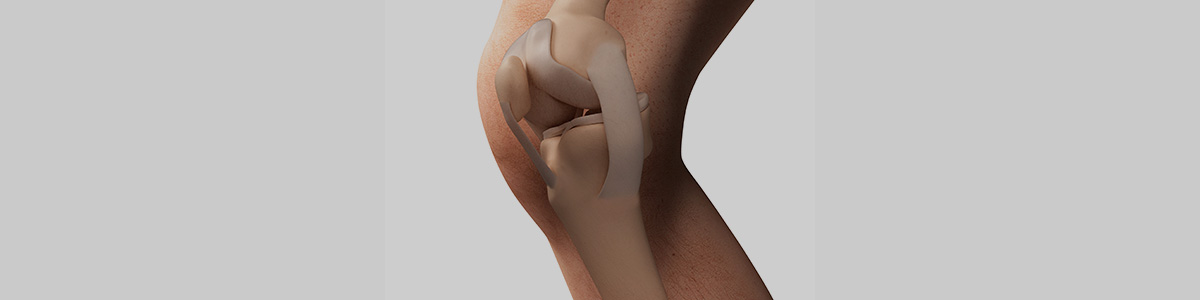

무릎관절은 대표적인 체중 지탱 관절로

무릎 사이에서 충격 흡수 기능을 하는 구조물을

반달 모양을 닮았다고 해서 반월상연골이라고 합니다.